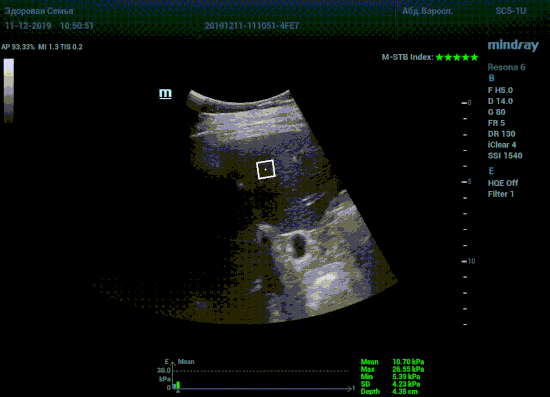

Что может дать ультразвуковое исследование печени помимо образований, гепатомегалии и цирроза? Диагностические системы, оснащенные функцией STQ (SoundTouchQuantification) имеют возможность регистрировать сдвиговые волны в паренхиме печени и оценить её эластичность. Такие возможности есть у систем серии Resona 6 и Resona 7 компании Mindray.

Определение плотности печени. Не ошибся ли оператор при измерении эластических свойств печени? Для оценки критериев качества предусмотрен индекс MBT, который покажет насколько «твердой» была рука оператора и двигалась ли печень. При MBT 5* рука тверда и показатели достоверны. Для оценки качества результатов используется IQR индекс, отображающий колебания показателей в точке измерения при расчете медианы. Показатели при IQR <30% считаются приемлемыми. Техника сканирования через межреберные промежутки требует размещение окна интереса на несколько сантиметром ниже капсулы, для исключения эффекта реверберации. Установка ROI на паренхиму без захвата сосудов, для исключения погрешностей измерения.